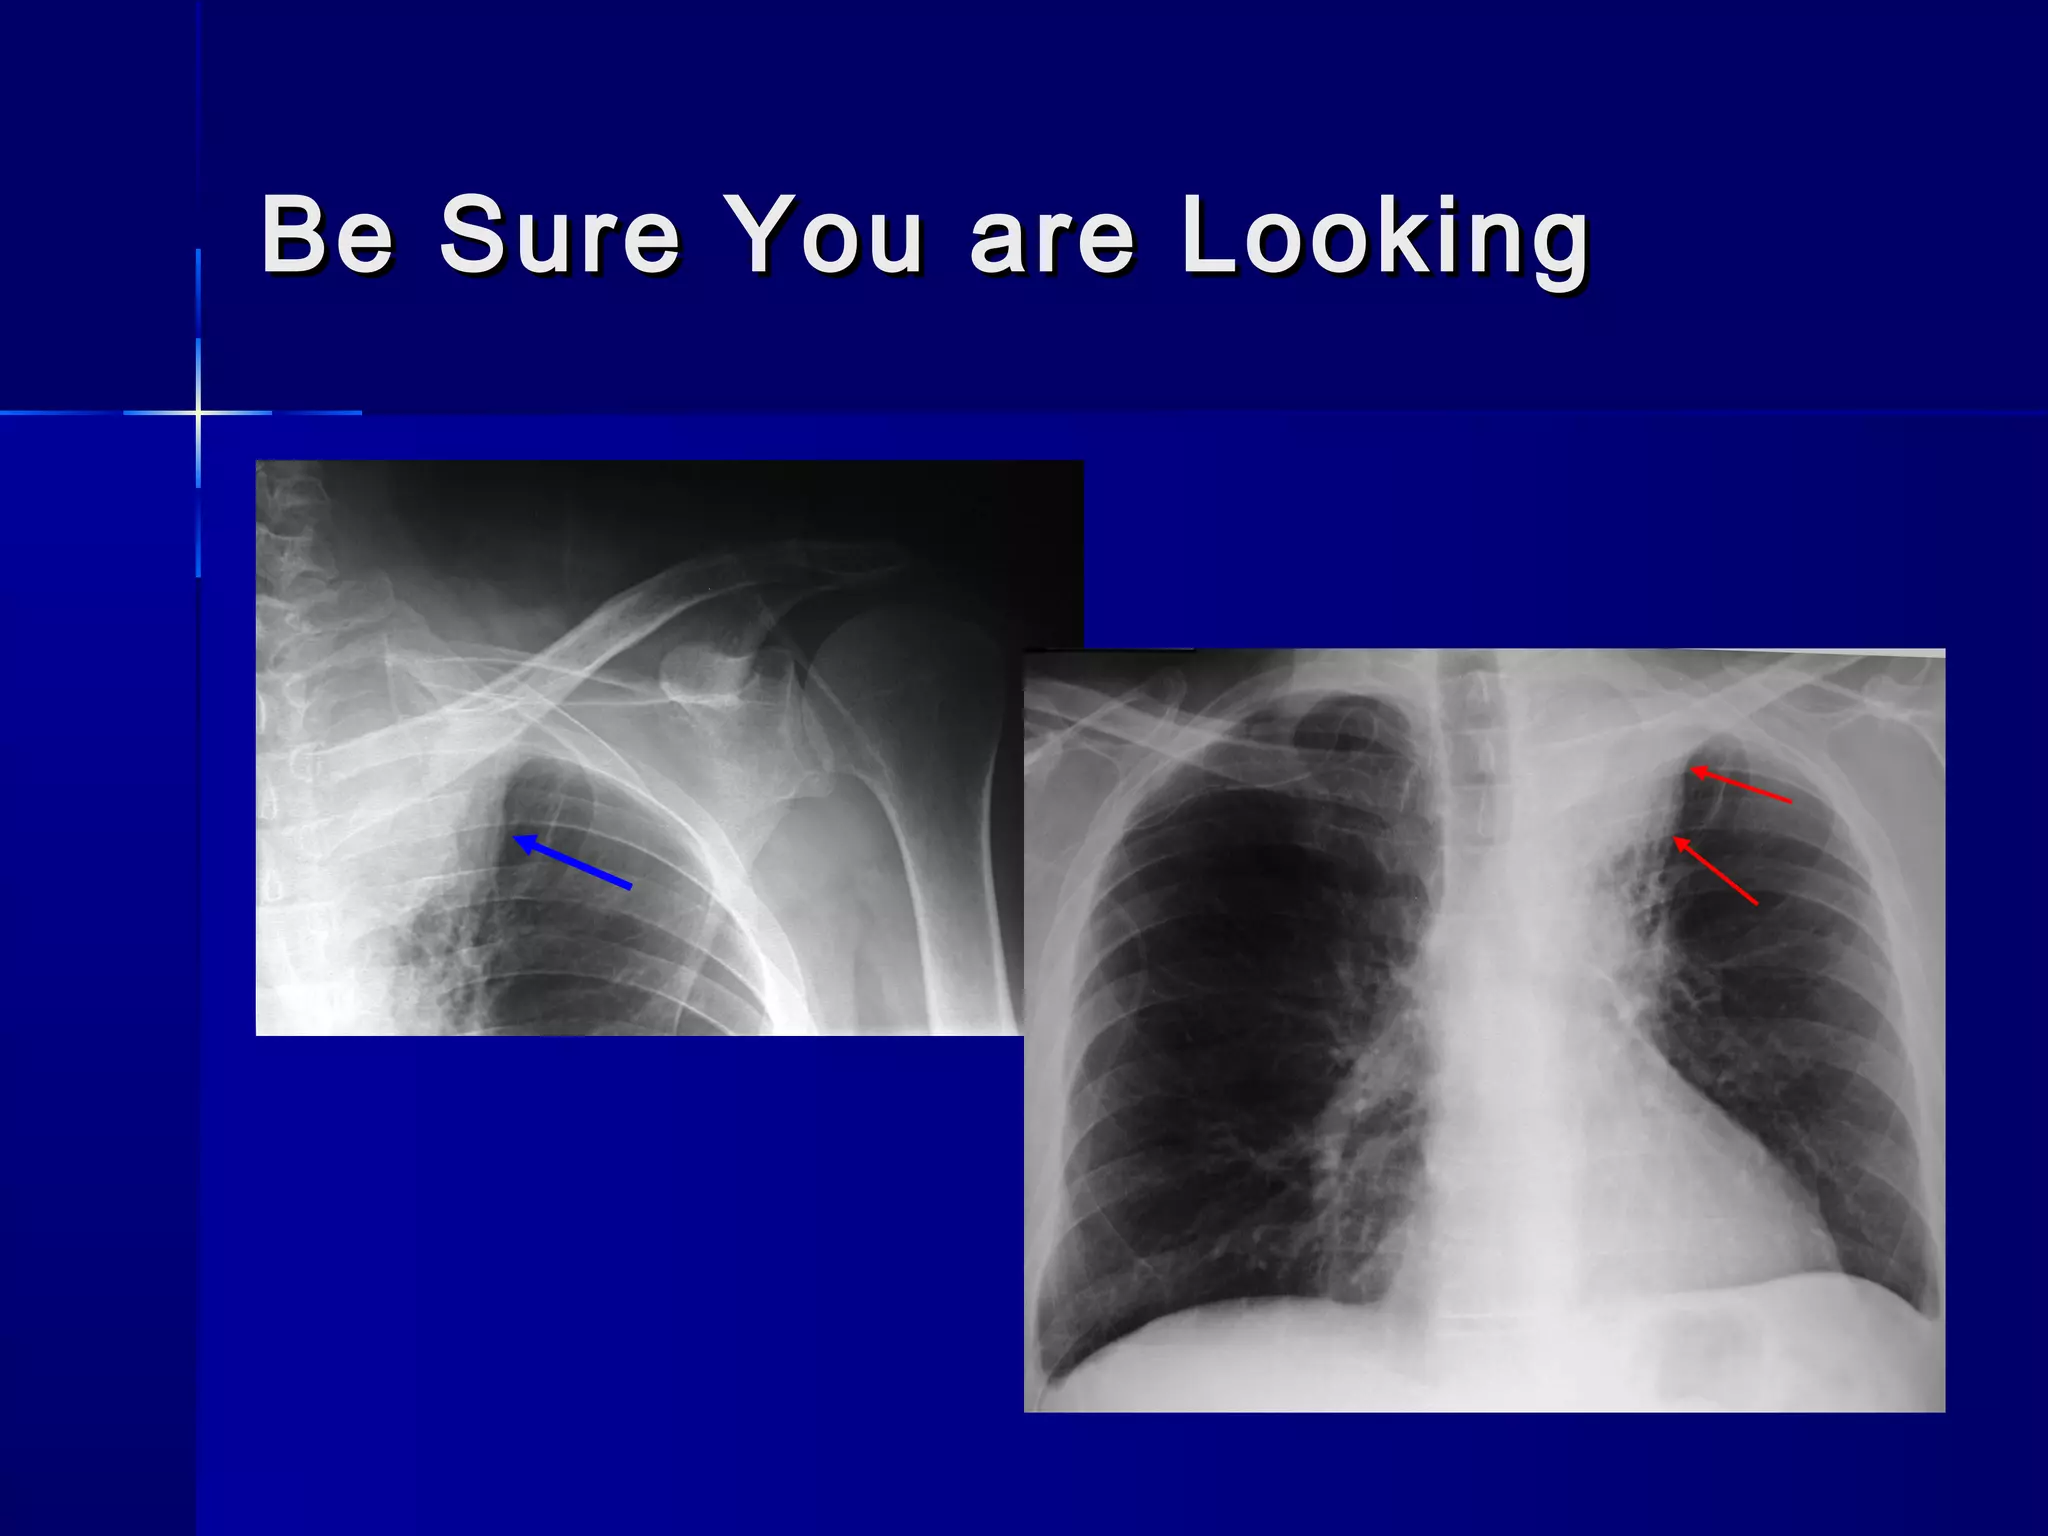

Be Sure You are LookingBe Sure You are Looking

Be Sure Youare LookingBe Sure You are Looking